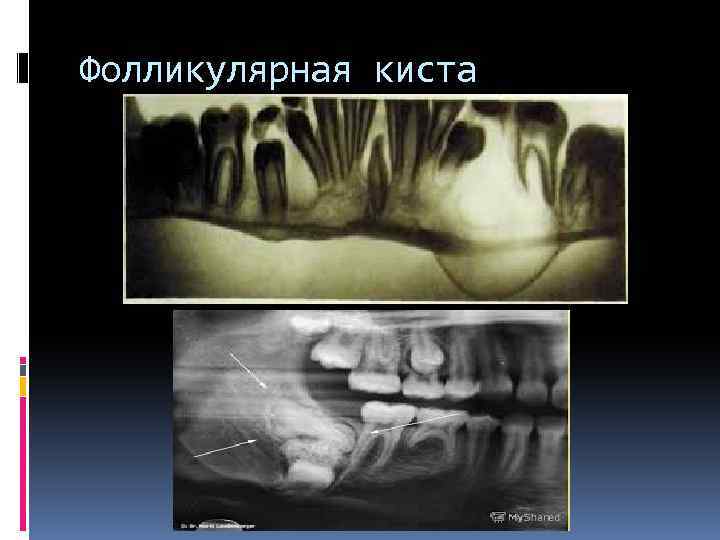

Фолликулярная киста